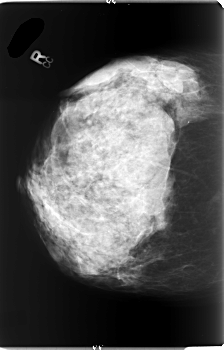

B_3006_1.RIGHT_MLO

RIGHT_MLO LINES 6000 PIXELS_PER_LINE 3536 BITS_PER_PIXEL 12 RESOLUTION 50 NON_OVERLAY